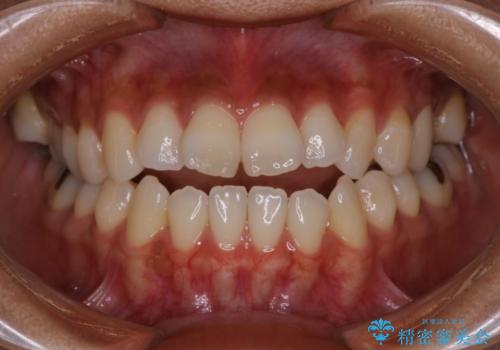

【審美装置】前歯で噛めない!抜歯しないで治したい

MARPEで非抜歯矯正|オープンバイトと八重歯を改善